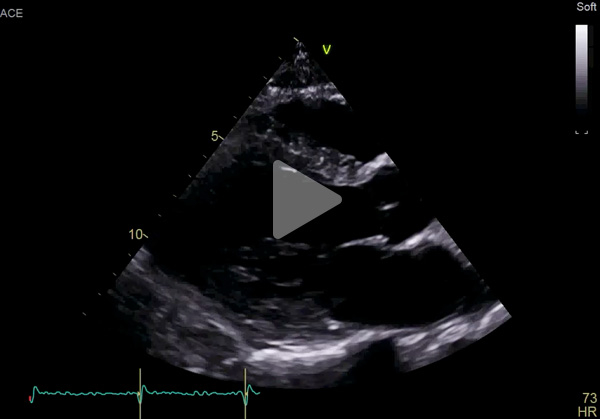

ETT :

- Hypertrophie ventriculaire gauche à prédominance septale (SIVd 12 mm, PPVG 12 mm) sans obstruction de repos, de fonction systolique conservée à 60 % en Simpson biplan. Cinétique homogène, SLG altéré à - 16 % en cocarde

- Profil mitral restrictif

- VD fin de bonne fonction longitudinale

- Pas de dilatation du massif atrial

- Pas de valvulopathie mitroaortique significative. Aorte ascendante non dilatée

- Veine cave inférieure fine respirante. Péricarde sec

Vidéo 1 : PSGA